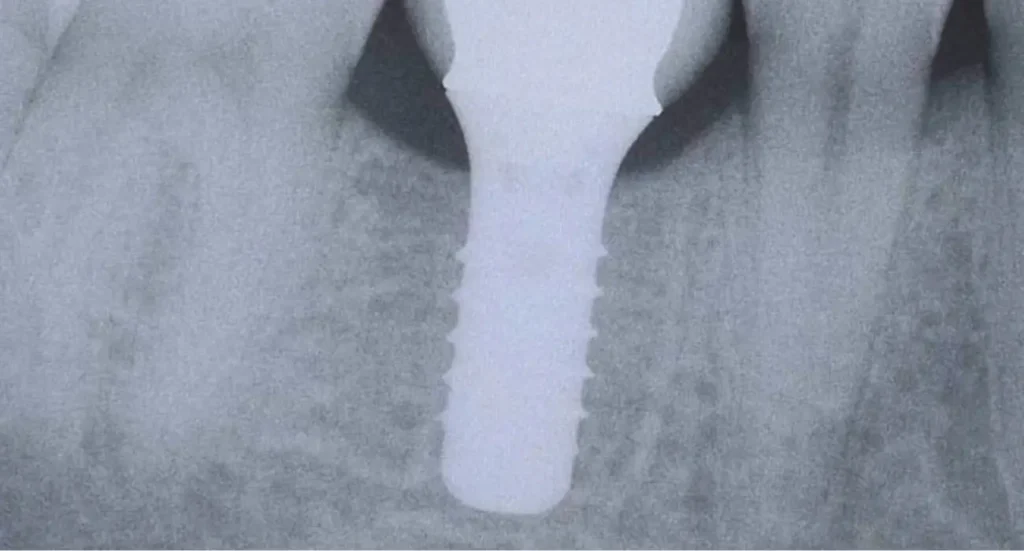

Un implant dentaire est une racine artificielle généralement en titane, que le chirurgien insère dans l’os de la mâchoire à l’endroit d’une dent manquante.

Une fois l’implant posé, il s’intègre solidement à l’os par un processus appelé ostéointégration (le titane fusionne avec l’os sur quelques semaines), ce qui le rend extrêmement stable.

On vient ensuite fixer sur cet implant une couronne prothétique pour remplacer la dent absente.